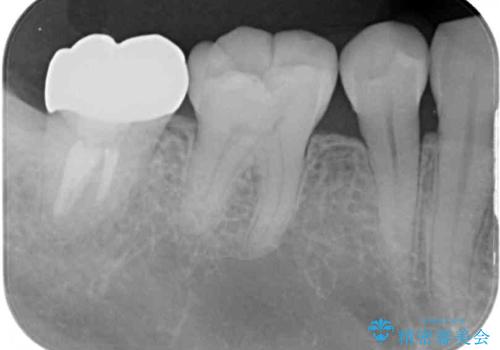

- 根管治療の専門医院で根管治療を行った後、セラミッククラウンによる補綴治療を希望して来院された患者様です。

根管治療後の土台も構築されていたので、仮歯に置き換えた後にフルジルコニアクラウンにて補綴することとしました。

遠心の歯肉が盛り上がっていたため、清掃性が悪くなる懸念がありましたが、クラウン装着による歯肉の腫れは認められませんでした。